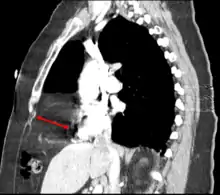

This rare anterior defect of the diaphragm is variably referred to as a Morgagni, retrosternal, or parasternal hernia. Accounting for approximately 2% of all CDH cases, it is characterized by herniation through the foramina of Morgagni which are located immediately adjacent and posterior to the xiphoid process of the sternum.[4]